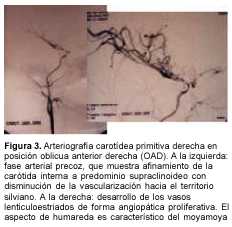

A los 3 meses de edad consultó por hemiplejia izquierda y retraso psicomotor. La tomografía computada (TC) de cráneo demostró un infarto hemisférico derecho (figura 1). Los estudios complementarios pusieron de manifiesto una coartación de aorta torácica descendente, sin evidencia de patología arterial sistémica. A nivel encefálico se estudió con angiografía de cuatro vasos de cuello, que demostró la existencia de una enfermedad de moyamoya (figuras 2 a 4). En ese momento no se consideró el tratamiento quirúrgico y una vez estabilizada se otorgó el alta. La coartación de la aorta no requirió cirugía y no se investigó el eventual nexo con la enfermedad de moyamoya. A los 8 meses de edad comenzó con hemiparesia derecha progresiva, lo que junto a su hemiplejia izquierda agravó su déficit motor severamente. Ingresó al Centro Hospitalario Pereira Rossell a los 10 meses. El examen del ingreso mostraba retardo neuropsíquico, hemiplejia izquierda espástica y hemiparesia derecha severa, que apenas vencía gravedad y no oponía resistencia. Una nueva TC mostró como elemento agregado al infarto derecho previo, una isquemia hemisférica izquierda (figura 5). Se resolvió realizar una revascularización quirúrgica del hemisferio izquierdo. Se intervino (figura 6) en el Servicio de Neurocirugía Pediátrica del Hospital. El procedimiento realizado fue una pialsinangiosis, con disección de la arteria temporal superficial izquierda con galea satélite y la sutura del tejido periarterial a la aracnoides temporal. La evolución posoperatoria fue buena, con recuperación progresiva de la función motora del hemicuerpo derecho. En forma gradual también comenzó a recuperar motricidad de su hemicuerpo izquierdo, anteriormente pléjico, y a mejorar sus performances, comenzando a pronunciar palabras a los cuatro meses, aunque manteniendo un retraso en el desarrollo psicomotor. Al año de operada se constató leve hemiparesia izquierda, ausencia de elementos deficitarios motores a derecha y persistencia de alteraciones en el lenguaje. Una ARM realizada a los diez meses de la operación mostró desarrollo de circulación colateral hacia el área quirúrgica (figura 7). Una TC de control permitió ver el infarto secuelar de hemisferio derecho y disminución franca de la hipodensidad del hemisferio izquierdo a los 18 meses de operada (figuras 8 y 9).